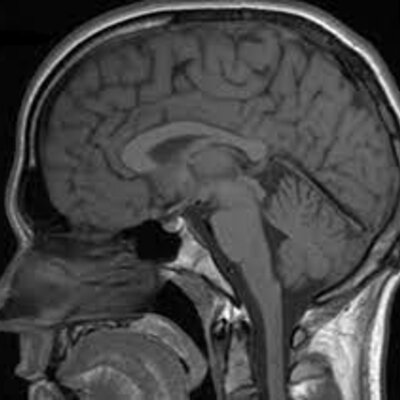

Historia de la resonancia magnética